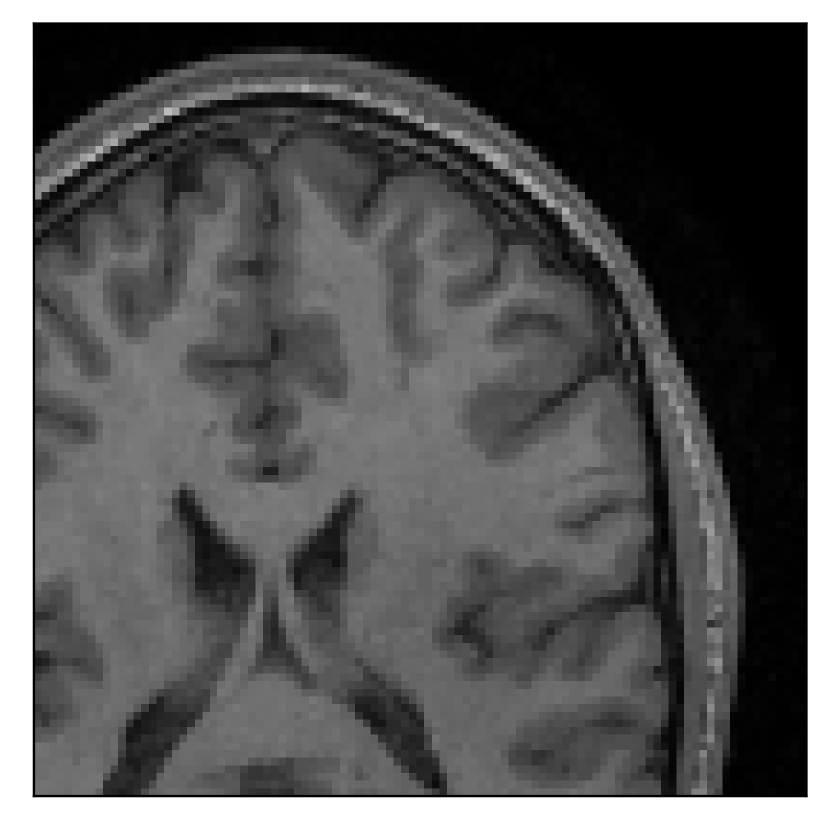

The second experiment is set up similarly to the previous one. We asked volunteer 3 to change position only once during the acquisition phase. We consider, now, a corrupted T2-FLAIR-weighted contrast with a reference T1-weighted contrast (see Table 1). The most important difference with the previous experiment, besides the type of contrast pair considered, is related to the randomized acquisition protocol. In this case, the scanner reconstruction employs a compressed-sensing reconstruction, and is not suited as input for the proposed motion-correction algorithm (see Appendix A). Therefore, for adequate motion correction, we must set up an intermediate step for processing the raw -space data via the SENSE reconstruction.

We further discuss the results of this experiment in Section 4.3.

4.3 Experiment 3: scanner reconstruction vs raw k-space data

The results of the two experiments described in Section 3.3 are depicted in Figures 12 and 14. The main difference between the two experiments is related to the input data for the proposed motion-correction algorithm.

In the case of randomized sampling, the scanner reconstruction is not adequate as input data for the proposed motion-correction algorithm, because it employs a compressed-sensing algorithm. We speculate that compressed-sensing reconstructions degrade the information contained in the corrupted volume, and the corrected contrast cannot be effectively recovered by simply removing rigid-motion artifacts (we defer the degraded results when using scanner reconstruction data in Appendix A). However, when the input data is obtained by directly processing the raw -space data via the SENSE reconstruction, the motion-correction scheme is able to successfully remove the motion artifacts (Figure 14).